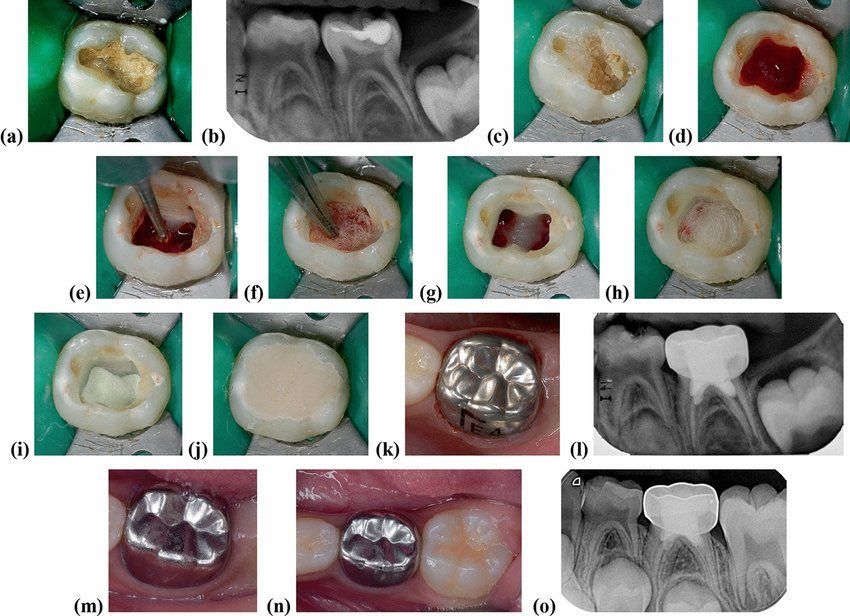

Pulpotomy with MTA

ضروري تاخذ اشعة قبل ما تبدأ لاسباب كثيرة حتى لو الاعرض كلها تقول انه العلاج بتر جزئي للب السن

حاول تشيل كل التسوس من الجدران السن قبل تفتح الحجرة اللبية لسن اسهل وانظف

لو حسيت ب drop عادي الامور طيبة لا تخاف، غير الbur من round لـ endo z ولا تخلي اي undercuts

من اسمه بتر اللب السني

الان اما بـ low speed او spoon excavator نشيل كل اللب يلي بالحجرة اللبية

لو وقف معك النزف تمام التمام لو لا ندخل بالـ orifice شوي 1-2 mm بستخدام small round bur low speed

احب اغسل ثم انه ما اجفف واحط قطنة تمتص، او من الاساس احط قطنة مبلولة بالحجرة اللبية

نشيلها ونحط MTA

قوامه المفروض يكون كانه عجينة نشكله مثل الكورة ونجيب قطنة مبلولة شوي ونضغط عليه

المفروض تغطي عندي كل orifice

خذ اشعة بعد عشان تقييم نفسك وتصير بالسجل عندك